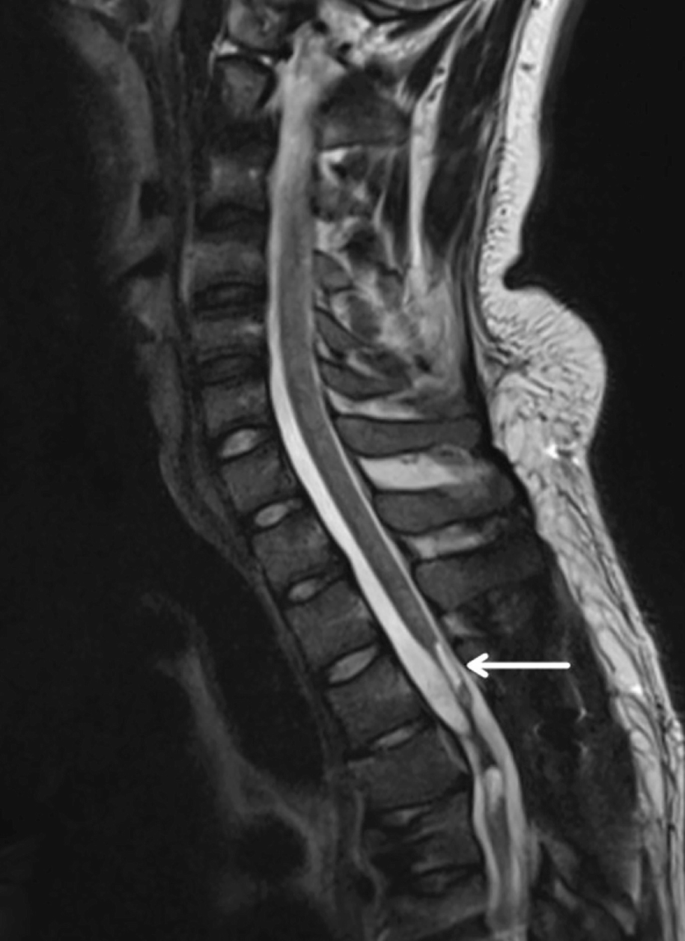

慢性期開(kāi)始于損傷后約3-6個(gè)月,并持續患者的余生,典型特征是囊腫形成和嚴重的神經(jīng)膠質(zhì)瘢痕(圖2)。

圖2:X射線(xiàn)圖像顯示慢性期脊髓損傷,通常以囊腫形成為特征,如白色箭頭所示